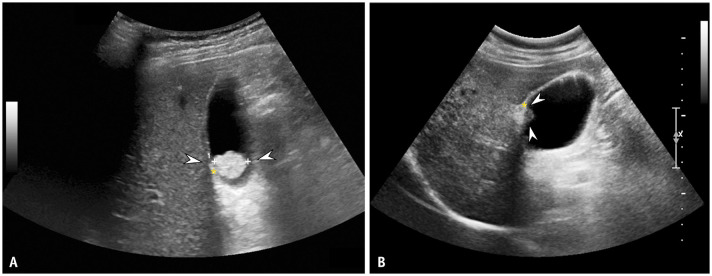

Abstract Image